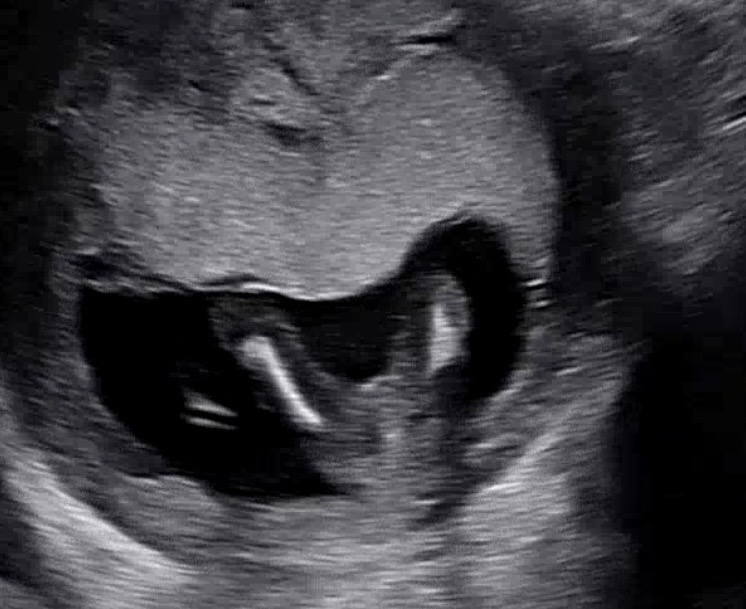

다리 사이 사진을 봐주세요!! 투표도 해주세요!!

15주 0일차.... 보여야 한다면 보여야 할 그것이 안보인답니닿ㅎ 안보옇욯 그쵸?? 다들 투표 한번씩 해주세요!!